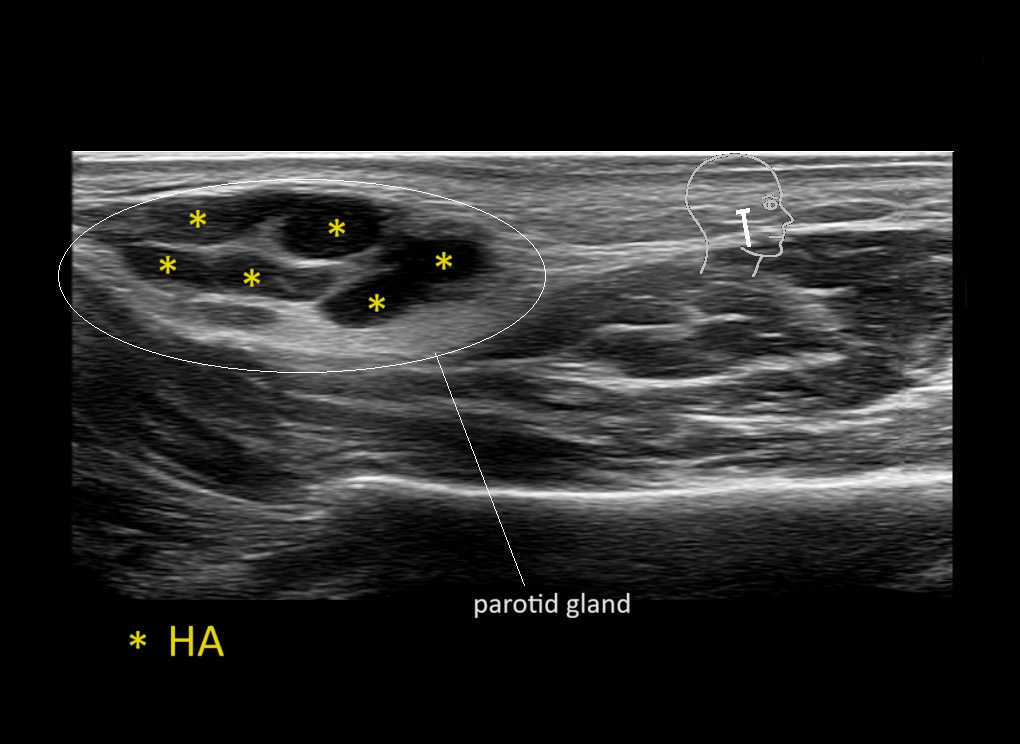

Parotid

Filler injections in the parotid gland may go unnoticed, however, inflammatory reactions and abscesses may occur. Hypervascularity can be seen with color doppler. Filler deposits are supposed to be injected into the superficial fatty layer . The space to inject into this layer may be limited. Routinely we measure a width of 2-4 millimeters with sometimes subcutaneous layers being less than one millimeter thick.

Study the first image to recognize the different layers. If you are sure about the layers, swipe to the second image to view the answer (if applicable).